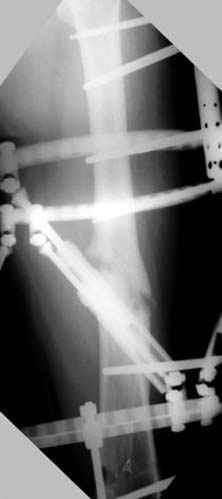

Отправитель: Djoldas Kuldjanov 23 Ноябрь 2004, 18:21

пластическая модель; и коррекция бедра аппаратом Илизарова.

Имею другие снимки тоже, получится как отчет о моей работе.

Отправитель: Evgueny Tschekashkin 23 Ноябрь 2004, 21:28

Почему не замена гвоздя с рассверливанием, а аппарат?

Отправитель: Alexander Chelnokov 23 Ноябрь 2004, 21:29

Попробую угадать - была инфекция?

Отправитель: Evgueny Tschekashkin 24 Ноябрь 2004, 21:09

хотя даже если бы и инфекция , то nail exchange с рассверливанием канала - вариант дебрайдмента) Я думаю, что последовательность развития событий:

Узкий к-м канал - тонкий гвоздь- усталостный перелом дистальных винтов - развитие нестабильности и как ее результат остеолиз вокруг гвоздя - деформация анатомической оси бедра. Похоже, что я понял почему аппарат, а не новый гвоздь:-)